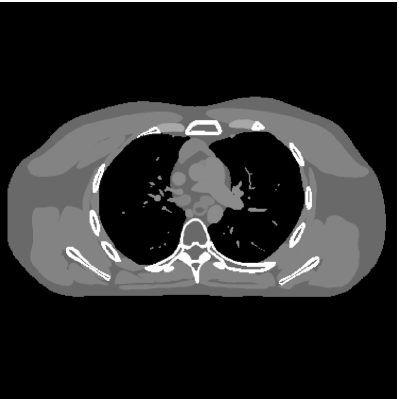

This paper was inspired by a simple observation related to our recent study [34]: for the penalized weighted-least squares (PWLS) reconstruction method using prior with a learned ST (PWLS-ST-) [34], the sparsification error histograms match a Laplace distribution over the iterations; see Fig. 1. The question then arises, “Does the learned prior experience model mismatch in testing stage?” To answer this question, we aim to investigate learned STs for regularization. This paper

The term denotes a -based sparsification error [3, 4, 5]. We expect to be more robust to sparsity model mismatch than the -based sparsification error used in [34, 36]. Fig. 1 shows histograms of sparsification error at different outer iterations of the PWLS-ST- method. Over the iterations, the sparsification error histograms appear more like a Laplace distribution than a Gaussian distribution. This observation suggests that the proposed prior model is more suitable than the prior model for PWLS-ST-based reconstruction. Section III-B1 shows that the proposed -based sparsification error term, , improves the accuracy of reconstruction compared to the prior model in [34, 36].

| @ outer iteration | @ outer iteration | @ outer iteration | @ outer iteration | |

|---|---|---|---|---|

| Probability density function |